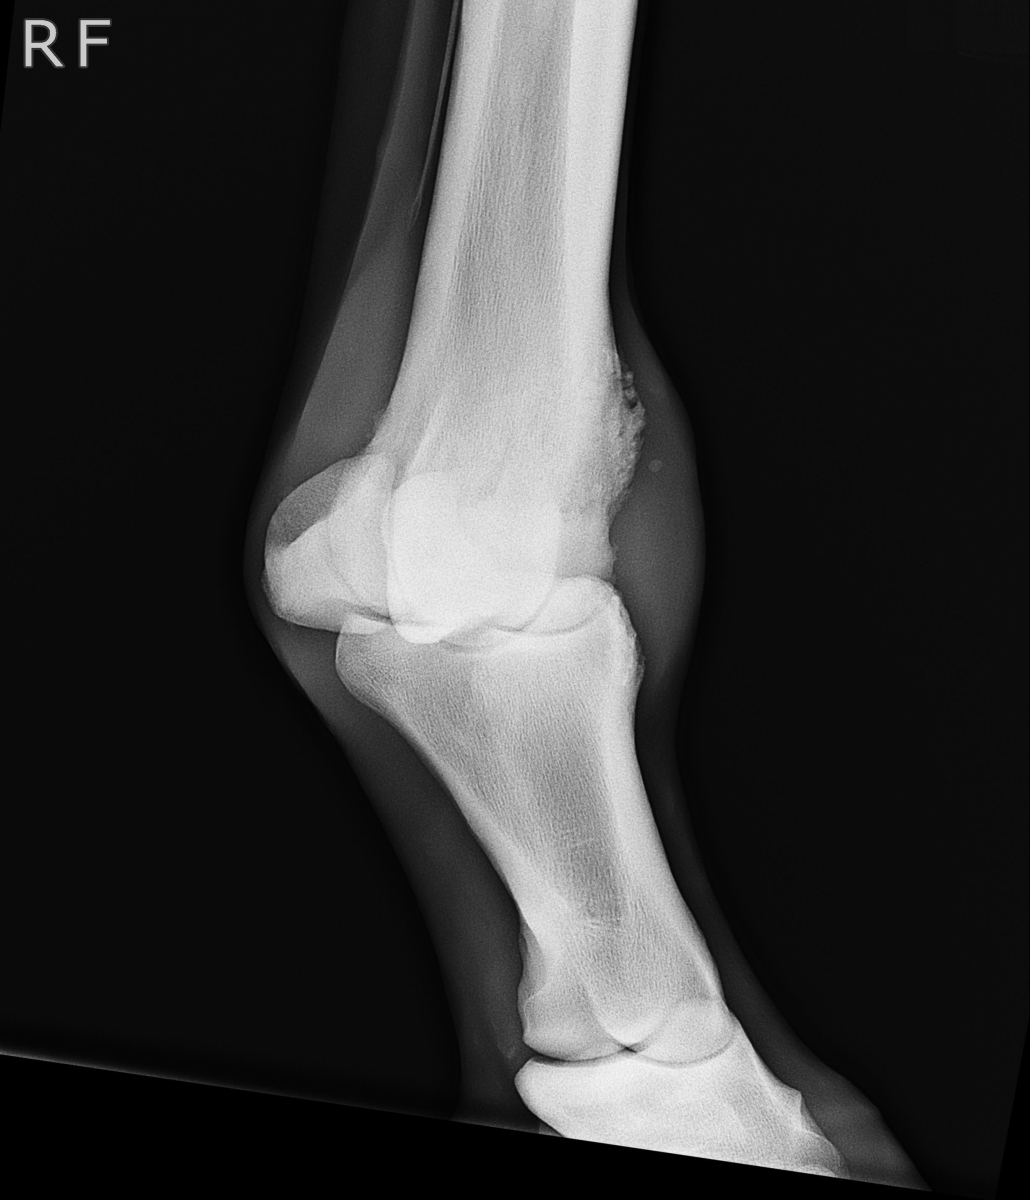

アユ号は笠松競馬、1月8日勝利後右前脚球節全面に骨膜炎が出ました。

X-Pも参考にしてください。